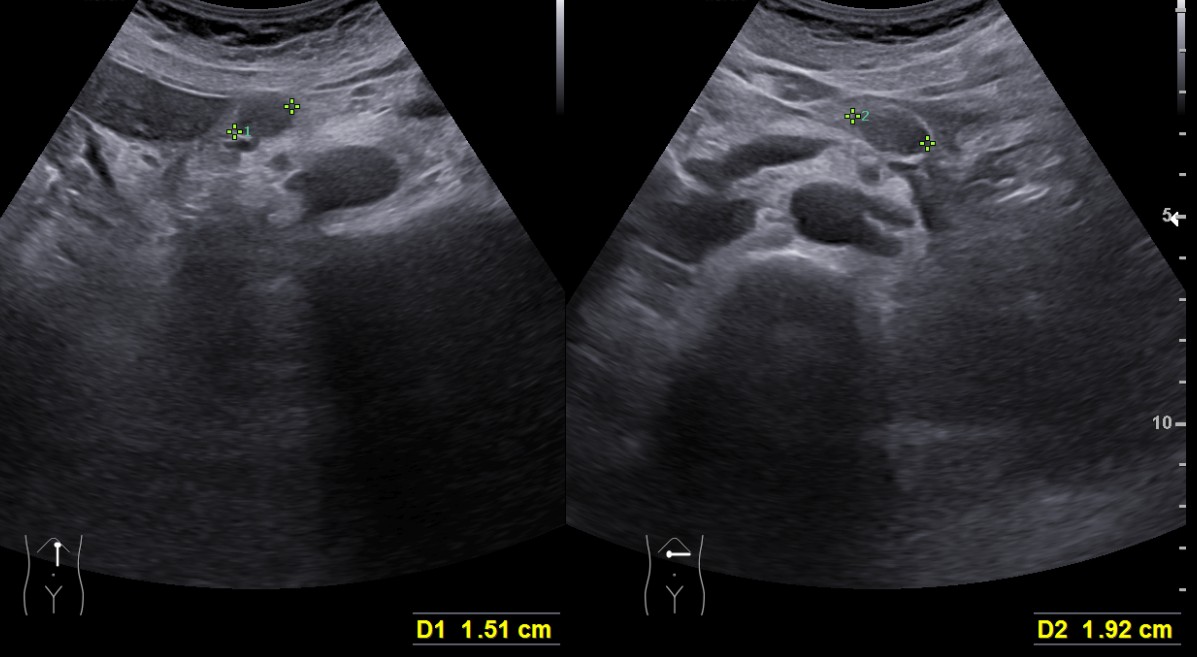

수개월 전부터 이유 없이 체중이 감소하여 시행한 복부 초음파 결과

췌장에 불균질 에코를 보이는 병변이 발견되어, 복부 CT 및 MRI를 시행하여

췌장암으로 진단한 증례입니다.